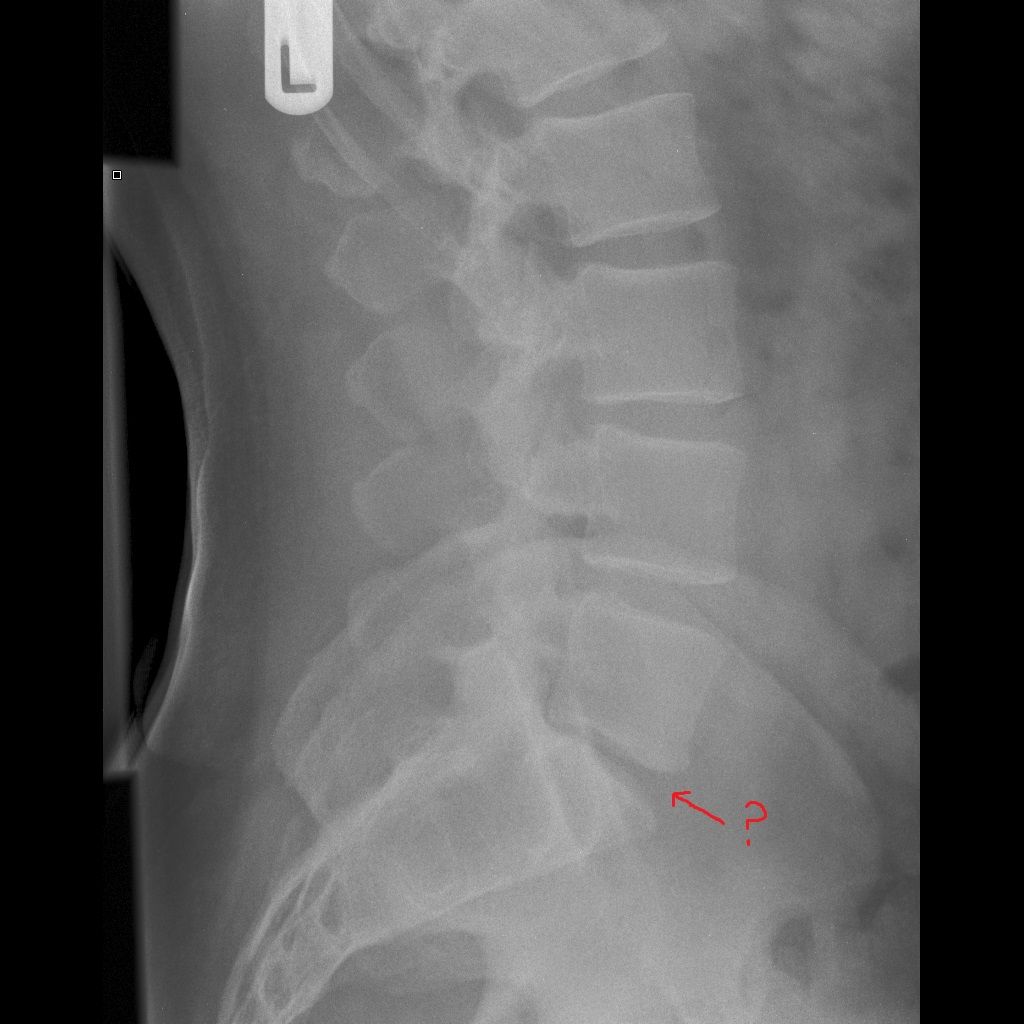

I provided the new Osteopath the Xrays and I highlighted my concern with the lack of space between L5 and S1 and does that indicate a problem with the disk? Osteopath said that people don't have a disk between L5-S1 so nothing to worry about.

Initially I was very pleasantly surprised, but later on I thought that doesn't seem right. All the images online show a disk there, or am I being thick? Any response appreciated.

Just answering the imaging question - Most people have a normal disc at L5/S1, though in some it is developmentally narrow. Unfortunately, unless you’ve had significant trauma (or you’re elderly and female) an x-ray is unlikely to help in diagnosing/managing your back pain hence Xrays aren’t usually recommended for back pain. Xrays will show wear and tear but everyone over 30 has wear and tear so the X-ray doesn’t get you any further.